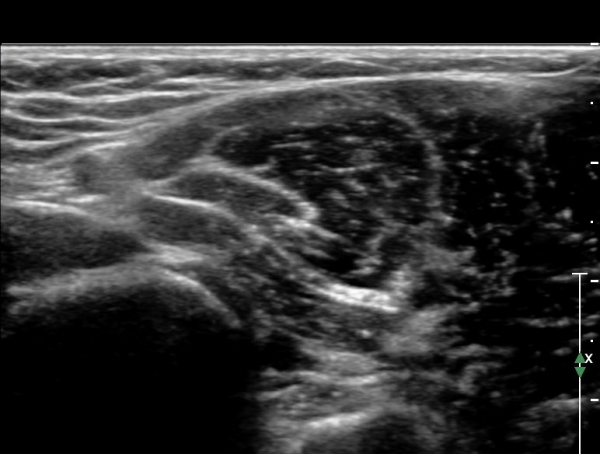

ÃÊÀ½ÆÄ °Ë»ç : ȸ³»±Ù ±ÙÀ§ºÎ¿¡¼ Á¤Á߽Űæ Ⱦ´Ü¸é°Å»ç¿¡¼ ƯÀÌ ¼Ò°ßÀ» º¸ÀÌÁö ¾ÊÀ¸³ª(»çÁø 1) ȸ³»±Ù ¿ä°ñµÎ ±â½ÃºÎ ¿¡¼ Á¤Á߽ŰæÀÇ ±¹°íÀû ¾Ð¹Ú ¹× ÆíÆòȰ¡ °üÂûµÊ(»çÁø 2). ÀÌ·± º¯È´Â °ÇÃø(»çÁø 5)°ú ºñ±³ÇÏ¸é ¶Ñ·ÇÇÔ.

Á¤Á߽Űæ Á¾´Ü¸é°Ë»ç¿¡¼ ȸ³»±Ù ¿ä°ñµÎ ±â½ÃºÎ¿¡¼ Á¤Á߽ŰæÀÇ ±¹¼ÒÀû ¾Ð¹Ú°ú Ç¥ÃþÀ¸·Î ÀüÀ§°¡ °üÂûµÇ°í ¾Ð¹ÚÀÇ ±ÙÀ§ºÎ¿¡¼´Â Á¤Áß½Å°æ ºÎÁ¾ÀÌ °üÂûµÊ(»çÁö 3). ÀÌ·± º¯È´Â °ÇÃø(»çÁø 6)°ú ºñ±³ÇÏ¸ç ¶Ñ·ÇÇÔ.